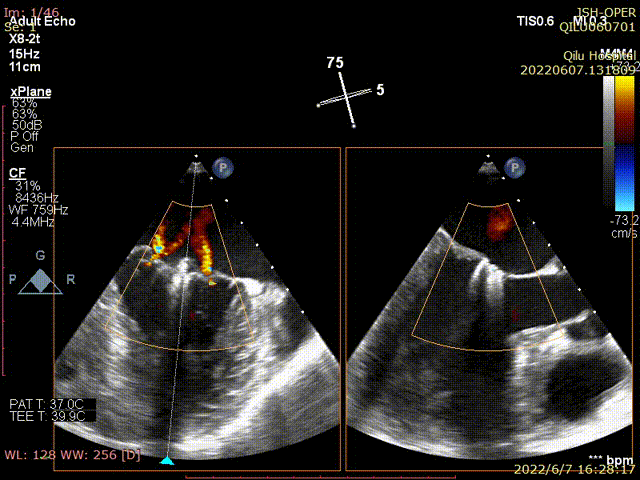

术前TEE显示二尖瓣重度反流,反流位置位于A2/P2区

术后TEE显示,二尖瓣夹植入后反流减少